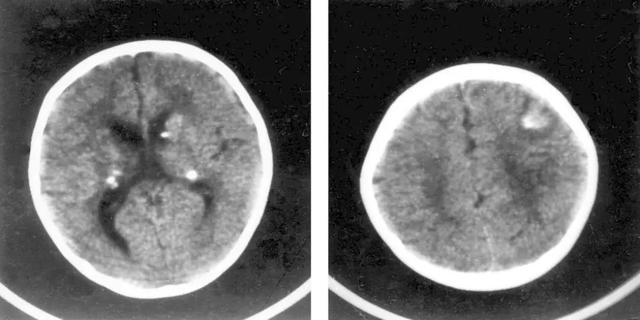

追踪病史,原来皮皮存在TSC1基因杂合突变,头颅MRI提示结节性硬化症病变。癫痫发作顽固并且难以控制,正是由TSC1基因突变所致神经罕见病结节性硬化症所引起的。

神经系统:癫痫发作、精神发育迟滞、自闭症、皮层下及室管膜下结节等。